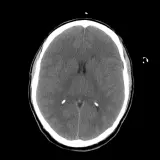

Over 2,100 interactive radiology cases, curated by radiologists for your level of training. Scroll, window, and view cases full screen — just like on PACS. Click linked findings in each writeup to jump straight to them on the image. Cases include sample reports, a focused discussion section, original illustrations, and videos.

Our site includes 3 main courses: Call Preparation, Introduction to Radiology, and Neuro Fellowship.

Intro to Radiology — a course coming later this year designed specifically for beginners. Terms are defined inline, lessons include introductory videos, and cases include guided video reviews by a radiologist who steps you through every finding. Lessons also include high-yield multiple choice questions that reinforce what you've learned and prepare you for boards.

Neuro Fellowship — a course tailored for fellows and practicing radiologists with in-depth reviews of advanced neuro topics like brain tumors, featuring rare diagnoses, differentials, and clinical pearls.